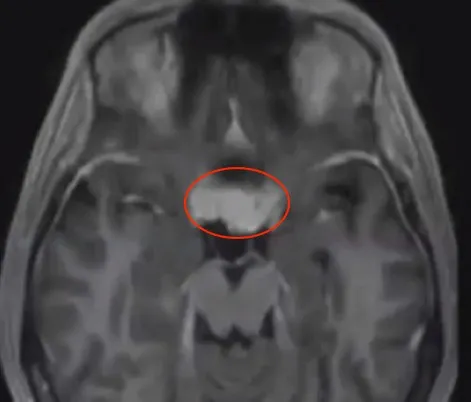

17岁那年,凯莉的右眼失去了光明,一个海绵窦区的肿瘤让她无可奈何。这个坚强的菇凉一直过着常人的生活,学习、工作,也成为了妻子和母亲。

直到多年后,这个肿瘤在悄悄生长下开始吞噬她左眼仅存的光明,视力一天比一天模煳……

术前影像

Dolenc教授对于Kaylee的情况,表示必须切除肿瘤,同时帮助她保全左侧视力,但是由于右眼失明17年,已经无法再恢复。